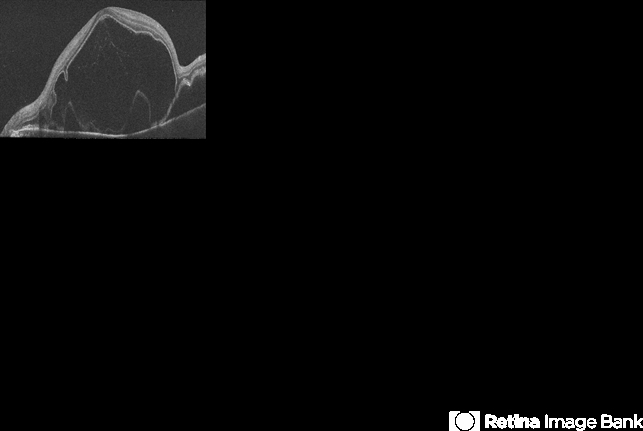

- Vogt-Koyanagi-Harada, serous retinal detachment, uveitis, exudative macula detachment

- Imaging device

Optical coherence tomography system

Zeiss Cirrus HD-OCT - Description

- SD-OCT imaging of an exudative detachment of the macula in a 27-year-old male diagnosed with Vogt-Koyanagi-Harada Syndrome.